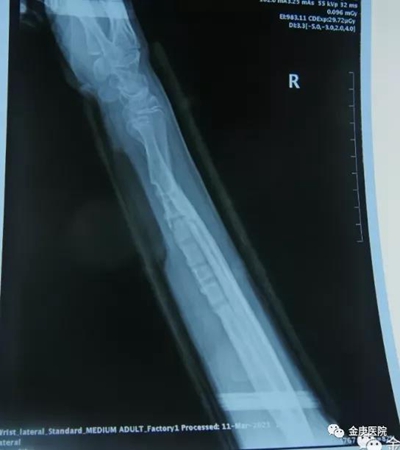

2021年3月,患者家長(zhǎng)慕名帶孩子來(lái)到金庚醫(yī)院找到了院長(zhǎng)宋兆普,他在外科專家徐發(fā)亮等配合下,只用了短短5分鐘時(shí)間,在不切口的情況下,完美將患者畸形尺骨斷開(kāi),而后又將橈骨與尺骨同時(shí)復(fù)位。從醫(yī)學(xué)檢查片看,對(duì)位可,手術(shù)成功,術(shù)后進(jìn)行外夾板固定,配合服用活血通絡(luò)和生骨接骨的院內(nèi)制劑,42天后,通過(guò)醫(yī)學(xué)檢查完全康復(fù)。

康復(fù)后的影像片

這例骨折部位斷開(kāi)復(fù)位術(shù),難點(diǎn)在于沒(méi)有切口的情況下,骨折部位的確定和斷開(kāi)復(fù)位時(shí)使用的力道,完全憑技術(shù)和多年的經(jīng)驗(yàn)積累,這種在許多醫(yī)院不可能完成的事,金庚醫(yī)院通過(guò)中醫(yī)傳統(tǒng)手法得以實(shí)現(xiàn),極大縮短患者康復(fù)周期和對(duì)患者的傷害,這是國(guó)家非遺項(xiàng)目宋氏中醫(yī)外科的神奇所在。